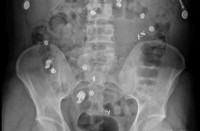

В большинстве случаев диагностика инородного тела кишечника незатруднительна. Важная роль принадлежит оценке жалоб пациента и анамнеза. Консультация гастроэнтеролога и хирурга позволяет предварительно оценить прогноз и определить тактику лечения, составить план обследования пациента. Обзорная рентгенография брюшной полости дает возможность визуализировать инородное тело, оценить его размеры и расположение. При инородных телах малых размеров, а также неконтрастирующихся при рентгенографии (например, из дерева, алюминия, пластмассы), проводится рентгеноскопия с введением контрастного вещества. Данный метод обследования позволяет не только обнаружить предмет, но и оценить проходимость кишечника.

В лабораторных анализах при отсутствии осложнений изменений нет, возможен лейкоцитоз. Для диагностики инородных тел кишечника, расположенных в толстом отделе, также применяется колоноскопия, при локализации в прямой кишке - пальцевое ректальное исследование, при его недостаточной информативности, подозрении на повреждение кишечника проводится ректороманоскопия.